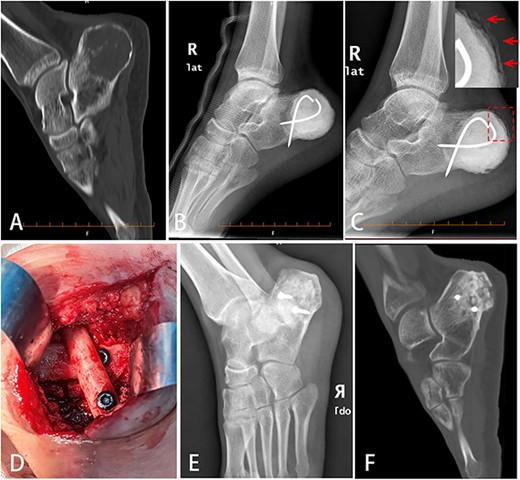

A 24-year-old man complained of pain in the right heel for more than 2 years without any trauma history. The right heel had mild swelling, and movement of ankle was slightly limited because of mild contracture of the Achilles tendon. X-ray of right foot showed low-density lesion on the posterior of calcaneus. CT scan showed an osteolytic destruction area of 4.1 × 3.0 × 3.9 cm with clear border and slight cortical discontinuity (Fig. 1A). The Musculoskeletal Tumor Score and American Orthopedic Foot and Ankle Society Hind Foot Score of this patient were 22 and 82 points, respectively, before surgery. Biopsy was performed and the pathological results showed benign tumor of chondroblastoma possibly. Ethical approval for this study was obtained from hospital Ethics Committee and the informed consent for the surgery was signed with the patient.

Bone defect reconstruction using Masquelet technique for calcaneal chondroblastoma. (A) X-ray showed osteolytic bone lesion located in posterior of right calcaneus body. The cortex was thinned because of tumor aggression. (B) After tumor was removed totally, bone cement (PMMA) was filled into the cavity and fixed with two cross Kirschner wires. (C) Six weeks later, the induced membrane on the calcaneal surface could be seen obviously (indicated by arrow). (D) Autologous fibular segment shoring and bone graft were filled into the cavity to reconstruct the defect. (E,F) Eleven months later, DR (E) and CT (F) scan showed good bone healing.

We choose Masquelet technique surgery for this patient. First, calcaneal tumor was totally removed by intralesional curettage. Local adjuvants included high-speed burring and 95% alcohol inactivation for 5 mins. Cortex defect of calcaneal was about 8 cm in longest diameter. Bone cement (PMMA) spacer was packed into the defect and fixed with two crossed Kirschner wires (Fig. 1B). Six weeks later, X-ray showed induced membrane around the bone cement surface (Fig. 1C). Second, bone cement was removed. Crossed autologous fibular segments (splitted in the middle) shoring with two screws and allogeneic cancellous graft associated with calcium phosphate and bone morphogenetic proteins (BMPs) were filled into the cavity to reconstruct the bone defect (Fig. 1D). The induced membrane wrapped the bone graft completely.

The patient’s postoperative recovery was good. The wound healed up in 2 weeks with no rejection reaction. Six weeks after surgery, the patient was able to walk with the help of single crutch. Three months later, the patient could walk by himself and ankle movement returned to normal. Six months later, the patient could walk freely without pain. Eleven months later, X-ray and CT scan showed no tumor relapse and good bone healing of calcaneus (Fig. 1E and F). The Musculoskeletal Tumor Score and American Orthopedic Foot and Ankle Society Hind Foot Score were up to 30 and 90 points, respectively. We have obtained the approval of the Ethics Committee and the written informed consent from patient before operation.